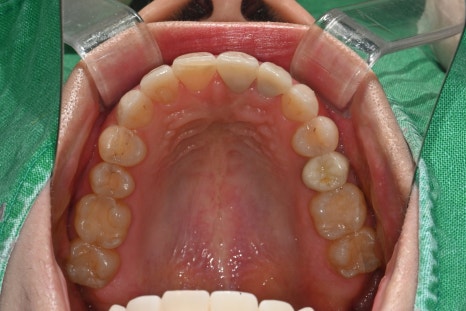

At the first visit, a panoramic image and oral photos were taken

to check the overall dental condition,

and because the color, translucency, and symmetry of the front tooth line

had a major impact on the overall impression,

we determined that a design combining laminate and anterior crowns

would be the most suitable.

- Shaping and scanning 4 abutments for OBZERO Pure laminate

Within the possible range, the amount of reduction was minimized,

and the exact form was captured with an intraoral scanner.